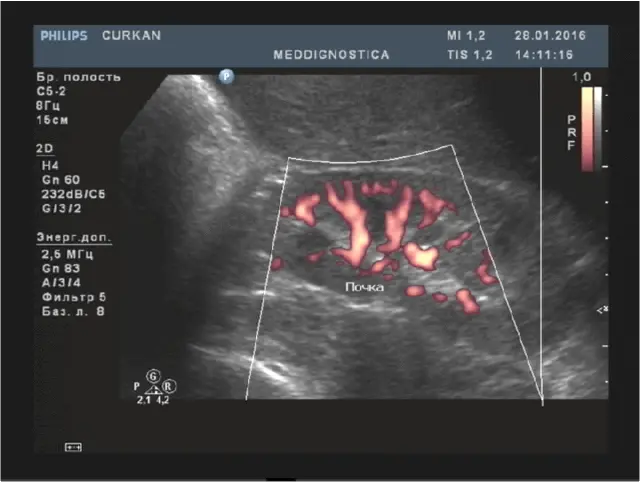

УЗД нирок на сьогоднішній день це високоінформативне, і в місці з тим, абсолютно безпечне і безболісне дослідження, що дозволяє досконально вивчити структуру нирок і визначити наявність в них дифузних і вогнищевих змін.

Нирки мають бобовидную форму, з рівними контурами, чіткими межами, капсула повинна бути не ущільнена. Паренхіма товщиною в середньому сегменті 12-20мм, корти-медулярная диференціація і диференціація паренхіма-нирковий синус збережена. Ехоструктури центрального комплексу однорідна, гіперехогенна, чашечно-лоханочная система не розширена, конкрементів не містить.